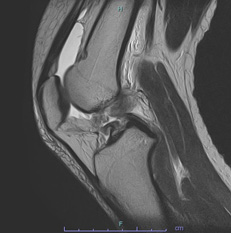

• 画像:損傷後外側半月板MRI画像(側面)

損傷後外側半月板MRI画像(側面)

• 画像:損傷後外側半月板MRI画像(正面)

損傷後外側半月板MRI画像(正面)